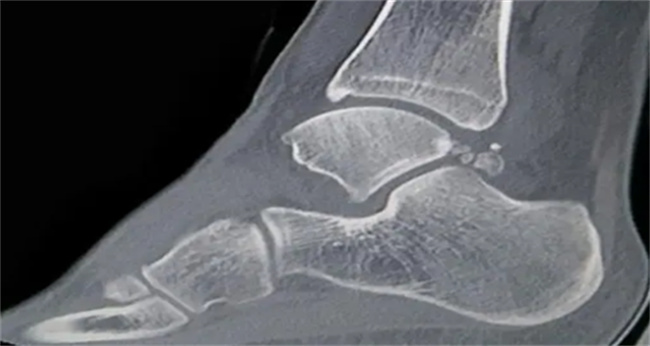

骨折和骨挫伤是骨科常见的两种损伤情况,它们的本质区别在于骨是否断裂。骨折是骨骼断裂的情况,而骨挫伤则是骨骼受到猛烈冲击或挤压导致骨骼表面产生碎裂。具体来说,骨折是指骨骼因受外力作用,而发生断裂的情况,骨折的类型有完全性骨折、不完全性骨折、开放性骨折等。骨折可以分为外伤性骨折和病理性骨折两类。外伤性骨折通常是因为肢体受到撞击、扭伤、摔倒、交通事故等外力导致的,而病理性骨折则是由于肿瘤、骨质疏松、骨髓炎等病理原因导致的。而骨挫伤则是指骨骼因受外力作用,而出现骨骼表面产生碎裂的情况,也称为骨皮质挫伤或骨皮质压迫性骨折。骨挫伤的症状比较轻微,通常不会出现明显的骨折症状,如骨移位等。